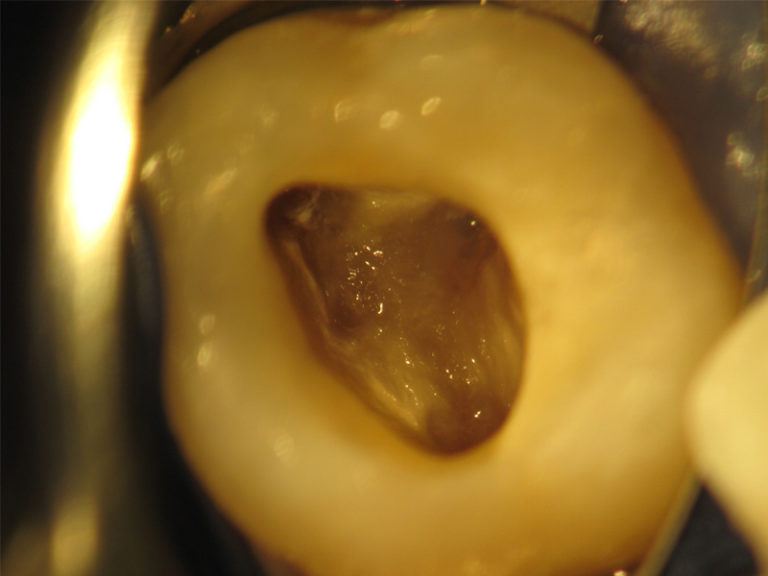

Anschließend wird das erkrankte Hartgewebe des Zahnes entfernt und durch eine Kunststoff- Aufbaufüllung ersetzt. Für den Zugang zu den feinen Kanalstrukturen wird eine kleine Öffnung in die Kaufläche des Zahns präpariert und die Wurzelkanaleingänge unter Einsatz des Dentalmikroskops dargestellt und erweitert. Es folgt die eletrometrische Zahnlängenbestimmung um sicherzustellen dass die Aufbereitung der Wurzelkanäle bis zum wirklichen Ende des Kanalsystems erfolgt. Bei diesem zurzeit genausten Verfahren der Zahnlängenbestimmung wird das Ende des Kanals mittels einer elektrischen Widerstandsmessung bestimmt.

Da das Wurzelkanalsystem einen komplizierten aufgebaut mit starken Krümmungen oder Verästelungen (vergleichbar mit einem Baum) aufweist, ist eine der Grundvoraussetzungen für eine erfolgreiche Revision das auffinden und die möglichst exakte mechanische und chemische Aufbereitung der Haupt sowie Seitkanäle.

Um die exakte mechanische und chemische Aufbereitung der Kanäle zu gewährleisten sind Vergrößerungshilfen wie das Dentalmikroskop eine Voraussetzung, um auch kleinste Details deutlich zu erkennen und substanzschonend behandeln zu können. Das Dentalmikroskop ermöglicht eine bis zu 30-fache Vergrößerung bei gleichzeitig idealen Beleuchtungsverhältnissen das Auffinden kleinster anatomischer Strukturen und in Verbindung mit sehr feinen Instrumenten das Arbeiten tief im Zahninnern.